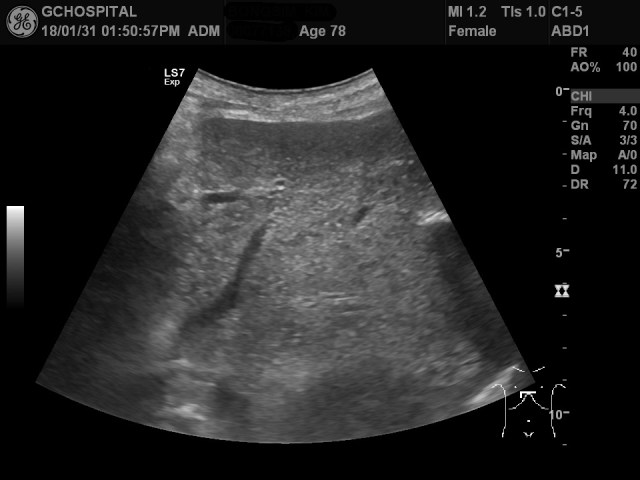

실제로 이 환자분은 탐촉자를 늑골 아래로 위치해서 접근하려 해도 늑골과 배 사이가 움푹 들어가 있기 때문에 탐촉자가 제대로 밀착될 수 없습니다. 그렇기때문에 위와 같이 굉장히 제한적인 영역만 관찰이 가능했습니다.

결국, 이 환자는 늑골 밑으로 접해서는 쓸개를 확인하는게 불가능했기 때문에 늑골 사이로 접근해서 영상을 얻을 수 밖에 없었습니다.

심한 지방간이 있었지만, 간실질의 깊은쪽 부분을 확인하는 것은 어렵지 않았으나, 간의 지붕부위를 확인하느게 쉽지 않았으며, 위 영상정도를 얻는게 최선이었습니다. 이 환자분의 경우에는 좌측 측와위자세에서보다 오히려, 누워 있는 자세에 간의 지붕부위를 더 쉽게 확인할 수 있었습니다.